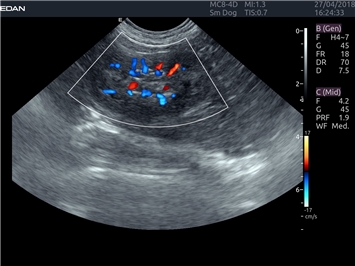

EDAN Acclarix LX4 VET

EDAN Acclarix LX4 VET представляет собой профессиональную ультразвуковую систему, специально разработанную для ветеринарных исследований. Сочетание стабильности, высокой производительности и эффективности делает эту систему идеальным выбором для современной ветеринарной практики.

Трехмерная реконструкция ЦДК:

Да

Цветовой допплер: